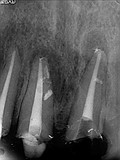

症例 1.

再治療ケース

10年以上前に根管治療を受けているが前歯部の違和感を主訴に受診。

土台はあるが根管充填材が入っておらず、根っこの先に病変(膿み袋)ができてしまっている。

先ずは歯質をあまり削除しないように土台を除去し無菌的処置を確実に行います。

治療前

治療中

治療後